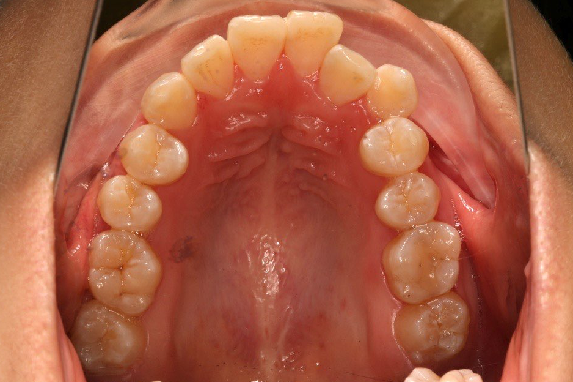

10 M after Post-Tx

10 M after Post-Tr

2019.08.06  术后  10个月复查

宏观评价:面部对称,面下三分一比例协调,上下唇凸度正常,上颌牙列内收转矩控制良好,下颌后缩改善,颏唇沟变得更加柔和,术后达到基本直面型。

迷你观评价:上下牙齿中线与面中线对齐,笑弧协调,微笑时牙龈暴露量正常,微笑时横向正常,左右唇基本对称。

微观评价:牙齿整齐,咬合关系良好,上下前牙转矩及突度控制良好,磨牙关系I类,尖窝咬合关系良好,OB,OJ正常。